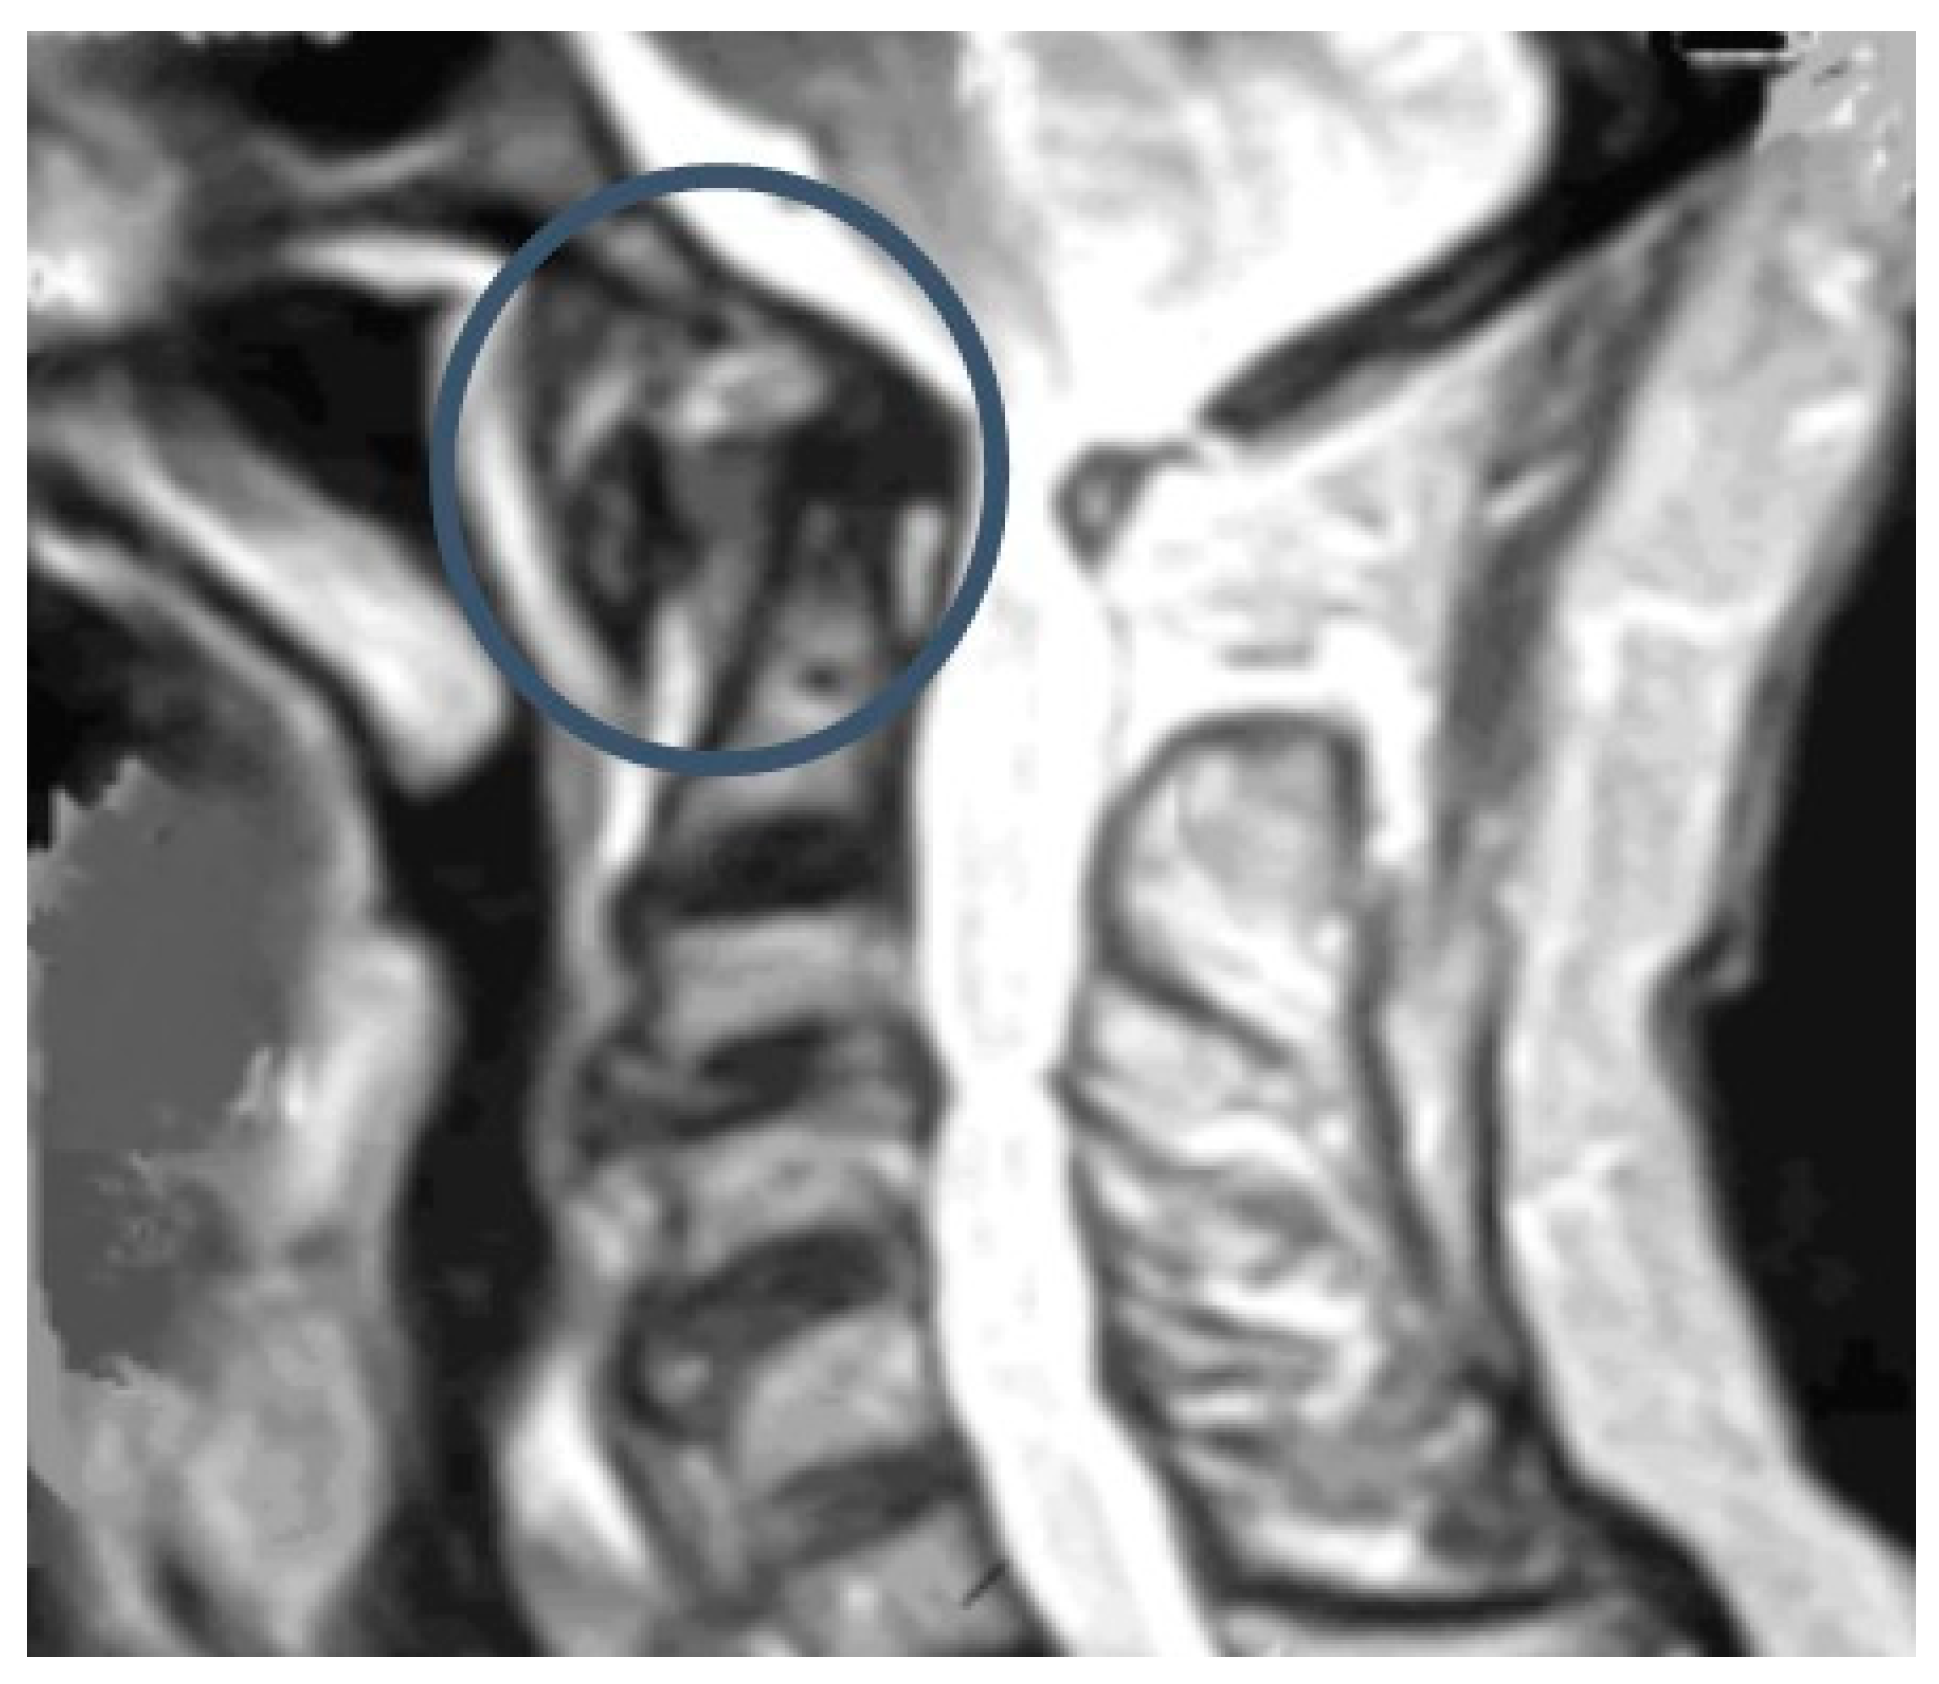

5.3. Magnetic Resonance Imaging (MRI)